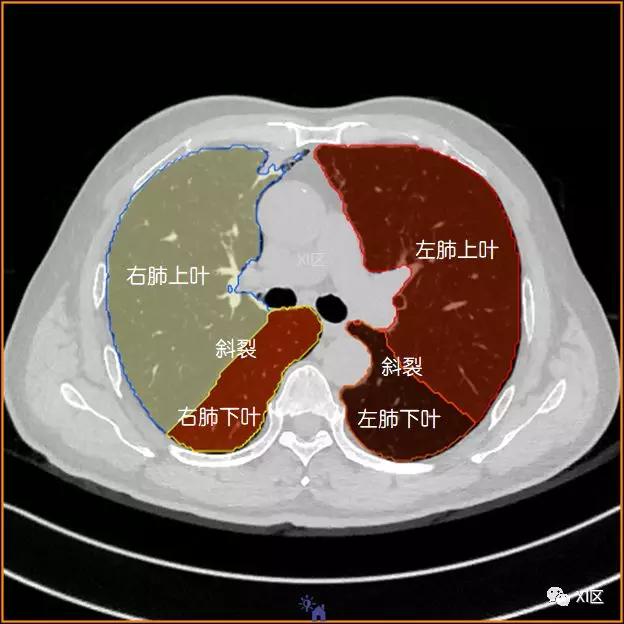

肺的分叶

左肺借斜裂成上、下两叶;右肺借斜裂和水平裂成上、中和下叶三叶。

横断位

肺的分段

肺的断层分段示意图

在进行肺的分段时,可以上下观察浏览,沿着相应气管的走形可以更容易准确地进行分段。